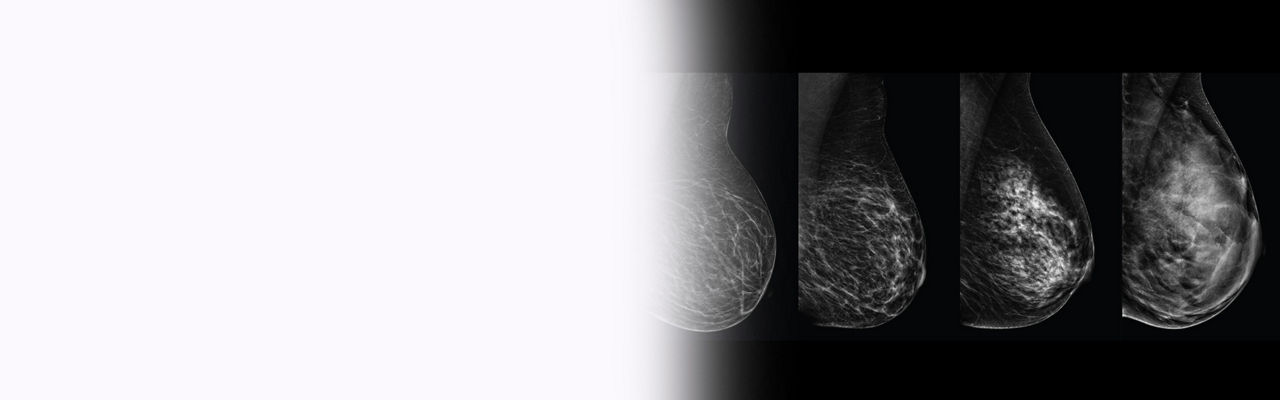

Improve breast cancer detection by 35.7% over mammography alone in dense breasts¹